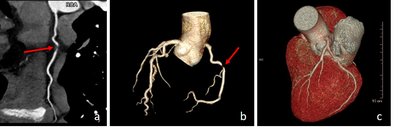

Die kardiale CT erlaubt eine anatomische Darstellung der Herzkranzgefäße, wie sie sonst nur durch eine invasive Herzkatheteruntersuchung möglich ist. Sie ist mittlerweile fester Bestandteil in der Diagnostik der koronaren Herzerkrankung. Mittels kardialer CT können bei korrekt ausgewählten Patienten zuverlässige Aussagen über das Vorhandensein von Engstellen bzw. Verschlüssen der Herzkranzgefäße und das Ausmaß von Gefäßverkalkungen getroffen werden. Somit lassen sich in bestimmten Fällen Herzkatheteruntersuchungen vermeiden. Bei Patienten mit bereits bekannter koronarer Herzerkrankung kann in ausgesuchten Fällen auch eine Darstellung von Bypassgefäßen oder Stents erfolgen.

Eine weitere Domäne der kardialen CT Diagnostik ist die Untersuchung und Darstellung von kongenitalen (angeborenen) Herzfehler. Diese lassen sich aufgrund der Möglichkeit der dreidimensionalen Darstellung meist deutlich besser mit der kardialen CT untersuchen, als in einer Herzkatheteruntersuchung.

Kardiales MRT: a) Normalbefund, b) ischämischer Myokardinfarkt im Stromgebiet des Ramus circumflexus (roter Pfeil), c) ausgeprägte Perimyokarditis mit Nekrosen (gelber Pfeil)